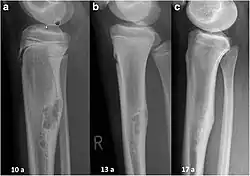

Non-ossifying fibroma of tibia | |

The most common bone tumor is a non-ossifying fibroma.[4] Average five-year survival in the United States after being diagnosed with bone and joint cancer is 67%.[5] The earliest known bone tumor was an osteosarcoma in a foot bone discovered in South Africa, between 1.6 and 1.8 million years ago.[6]

Primary bone tumors

Primary tumors of bone can be divided into benign tumors and cancers. Common benign bone tumors may be neoplastic, developmental, traumatic, infectious, or inflammatory in etiology. Some benign tumors are not true neoplasms, but rather, represent hamartomas, namely the osteochondroma. The most common locations for many primary tumors, both benign and malignant include the distal femur and proximal tibia (around the knee joint). Examples of benign bone tumors include osteoma, osteoid osteoma, osteochondroma, osteoblastoma, enchondroma, giant cell tumor of bone and aneurysmal bone cyst.